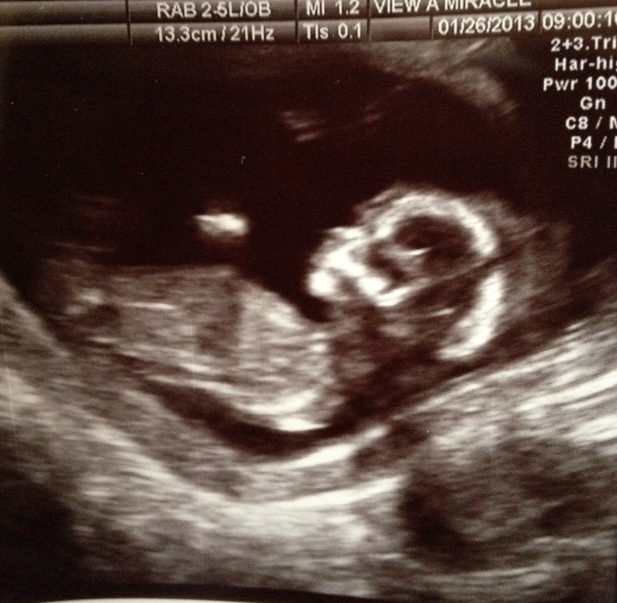

Ultrasound pic (13w5d)

Hi, I'm not sure where to post these or if people give their opinions on this forum or somewhere else but thought i would put my u/s pic from a scan i had this morn. It was at a private clinic where the lady has been doing this since 1993 and she said she was most certain my baby is a girl. She showed me the white line and said i was thin, etc so that i can be pretty reassured she is a she. I know it is early and was really just doing this for fun today but cant help but have a big smile on my face as this was most likely my last chance to have a daughter with all my fertility issues. We tried to do pgd and it didnt go very smoothly however we did do the erriccson sperm spinning. Cant wait to confirm at my anatomy scan. Take a look at my little princess..... fingers crossed!! :)

The first is a pic is the one from my 12 week scan. (is that considered a nub shot?) The tech thought he could tell me the sex at that scan too. The other is another pic taken at the scan i had at 13w5d....skull theory?